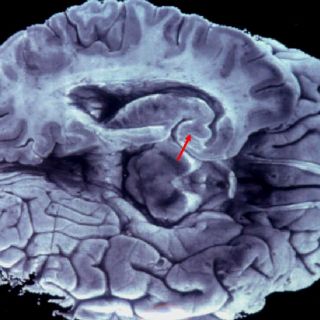

El estrés como una carga emocional mayor a 40 días afecta de manera severa al organismo

estrés como una carga emocional mayor a 40 días generada por la muerte de un familiar, deficiencia en el número de horas de sueño o una alimentación rica en grasas o carbohidratos pueden afectar de manera severa la resistencia natural del cerebro a la insulina.